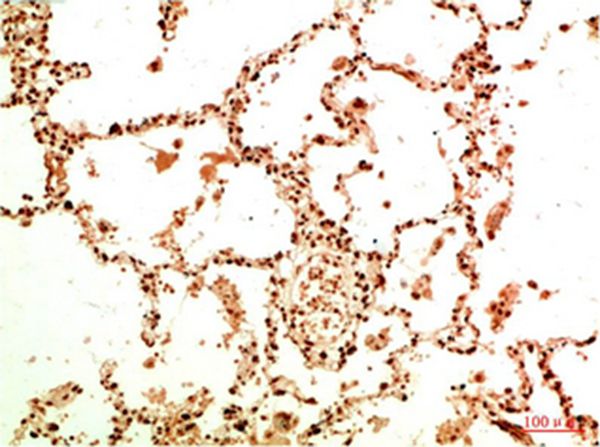

Immunohistochemical analysis of paraffin-embedded Human Lung Carcinoma Tissue using Acetyl NF kB P65(K314/K315) Mouse mAb diluted at 1:200.